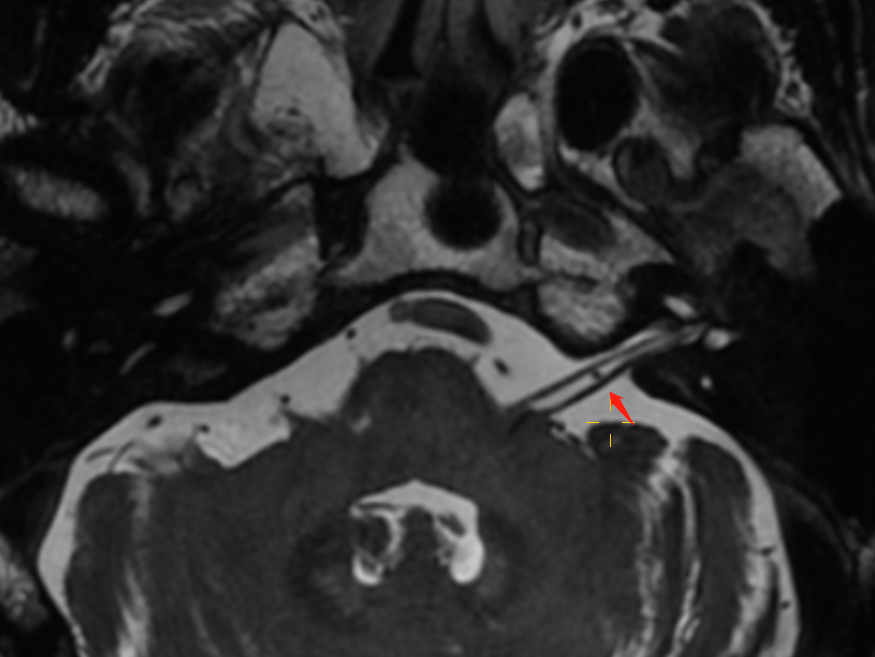

3DFIESTA 显示右侧小脑下前动脉穿行于面神经和前庭耳蜗神经间隙,并进入内耳道外口约 4 mm,神经与血管间隙消失,前庭耳蜗神经稍受压向外弯曲;左侧小脑下前动脉于内耳道外口穿行于面神经和前庭耳蜗神经间隙,局部接触、但无形态改变。

右小脑前下动脉迂曲延伸进入内听道神经与血管间隙消失,前庭耳蜗神经稍受压向外弯曲